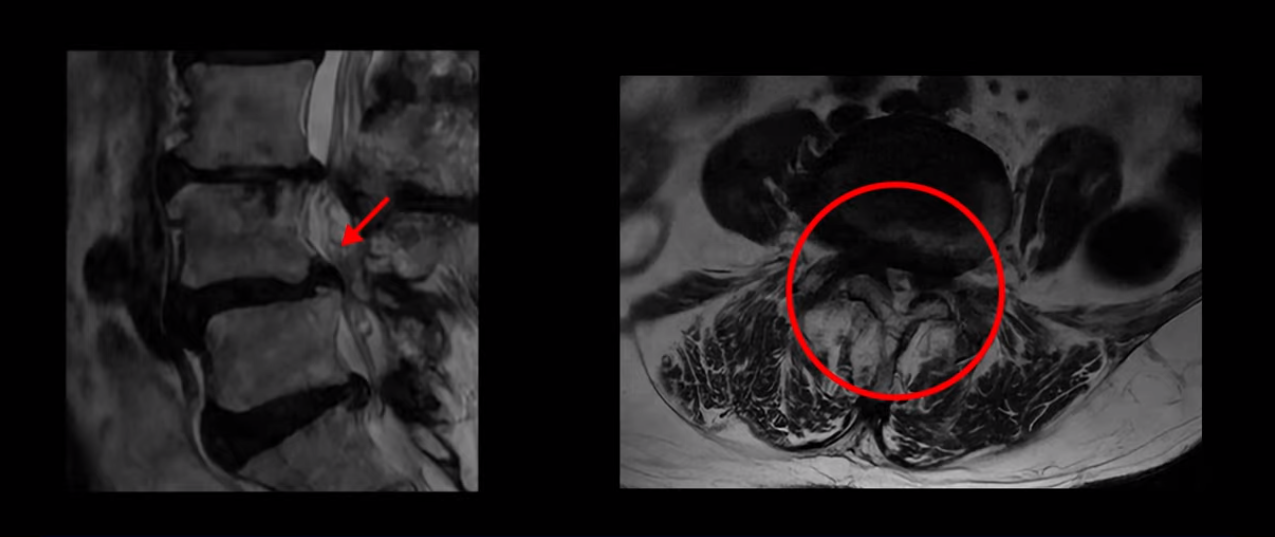

4번 5번 마디를 자세히 보면 심한 중심성 협착이 있어서 신경 구멍이 매우 좁아져 있습니다.

또 신경 가지가 빠져나가는 추간공도 매우 좁아져 있습니다.

그래서 양쪽 엉덩이가 아프고 다리는 발바닥까지 저리고 아프면서 발을 줄로 묶어놓은 것 같고 다리의 힘도 빠져 걷기가 어렵습니다.